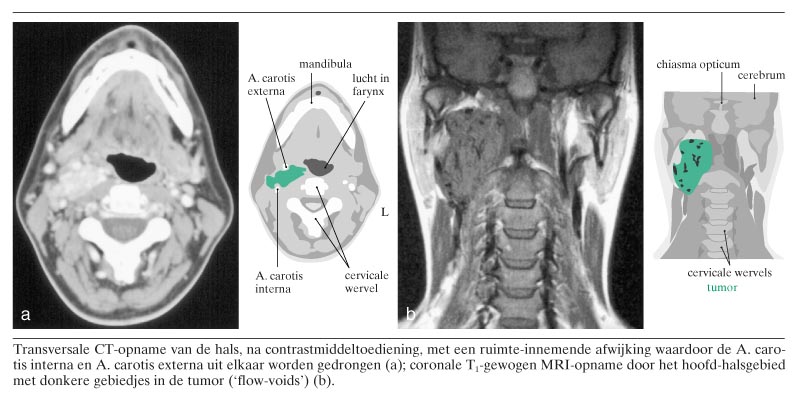

Een 33-jarige vrouw met een blanco voorgeschiedenis bemerkte een pijnloze zwelling rechts in de hals. Op een CT-scan, gemaakt na toediening van contrastmiddel, werd een grote massa rechts in de hals gezien welke een sterke aankleuring toonde en de A. carotis interna en A. carotis externa uiteenduwde (figuur). MRI toonde multipele donkere gebiedjes in de tumor, die overeenkwamen met stromend bloed (zogenaamde ‘flow-voids’, soms beschreven als ‘peper-en-zoutaspect’) (zie de figuur). Op basis van deze radiologische bevindingen luidde de diagnose ‘paraganglioom’. De paraganglia zijn groepen van gespecialiseerde chemoreceptorcellen, onder meer in de bijnieren, langs de A. carotis…